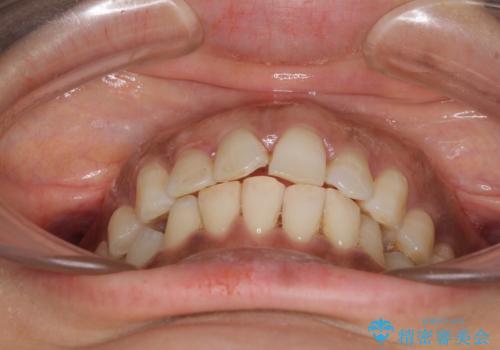

- 上下前歯のデコボコ改善をインビザラインにて行いたいとのことで来院された患者様です。

インビザラインをご希望のことで、IPR(歯と歯の間を削る)などによりスペースを獲得して、排列していくこととしました。

骨格的に上下顎が左右にずれていたため、正中位置は現状を維持したまま歯列不正を解消していくことになります。